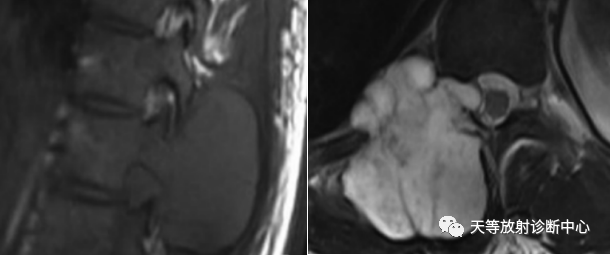

术后内固定支架

肿瘤复发,椎旁分叶状软组织肿块,内部信号不均,混杂信号,高低信号不等,内见线状小叶间隔。

DWI信号较高,内部钙化灶呈散在泥沙样低信号灶。

诊断软骨肉瘤复发。

1、骨破坏区位于椎体及附件区,溶骨性骨质破坏;

2、外生生长并形成软组织肿块

3、破坏与软组织不成比例,钙化出现多,钙化呈泥沙样,点状、块状、不规则型 ;

4、局部破入椎管内。

5、可见骨硬化。